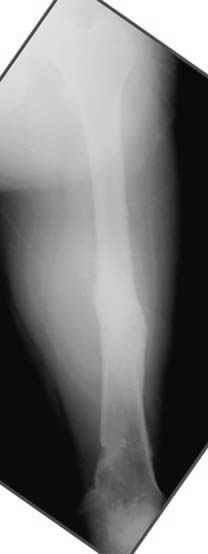

Отправитель: Djoldas Kuldjanov 23 Ноябрь 2004, 18:21

пластическая модель; и коррекция бедра аппаратом Илизарова.

Имею другие снимки тоже, получится как отчет о моей работе.

хотя даже если бы и инфекция , то nail exchange с рассверливанием канала - вариант дебрайдмента) Я думаю, что последовательность развития событий:

Узкий к-м канал - тонкий гвоздь- усталостный перелом дистальных винтов - развитие нестабильности и как ее результат остеолиз вокруг гвоздя - деформация анатомической оси бедра. Похоже, что я понял почему аппарат, а не новый гвоздь:-)